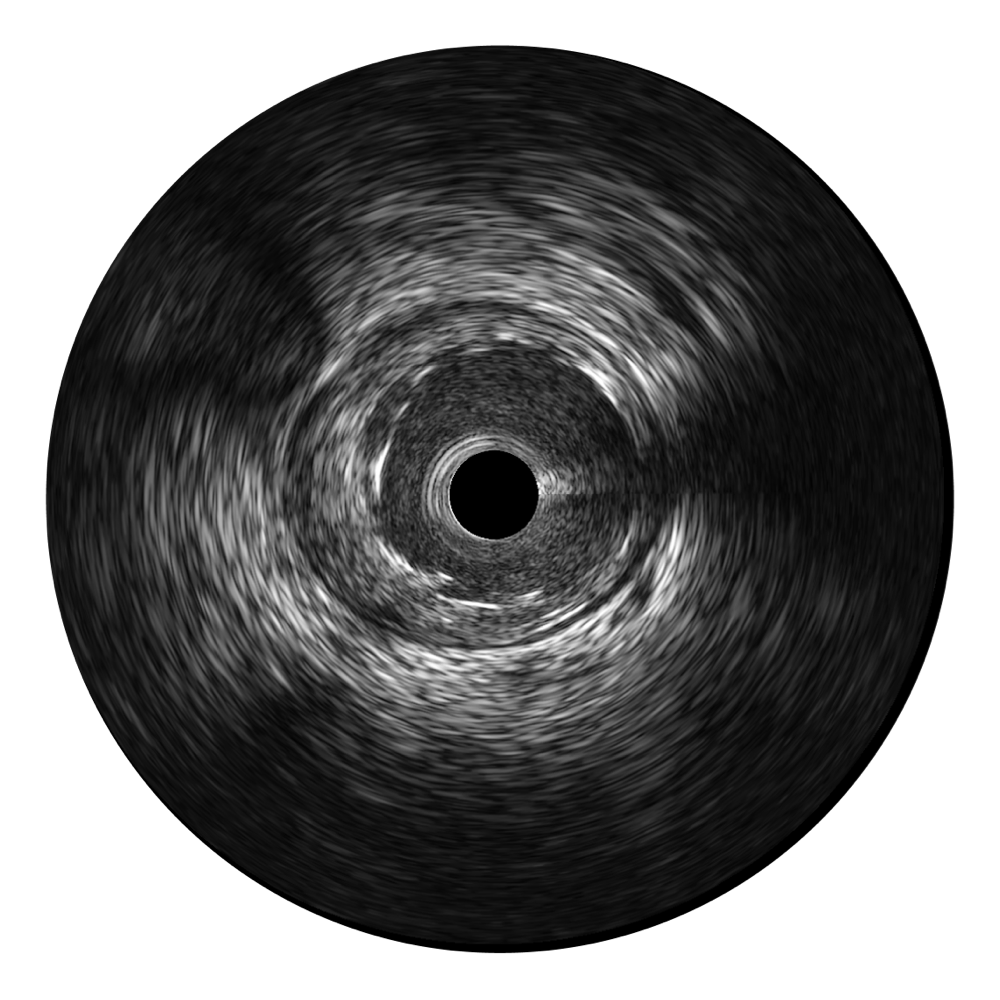

竞技宝(JJB)官方网站宽频IVUS图像

对比传统IVUS导管成像,竞技宝(JJB)官方网站宽频IVUS图像的近场支架梁显影更细腻,远场中膜外血管仍清晰可辨,兼顾远中近,兼顾分辨力与穿透深度